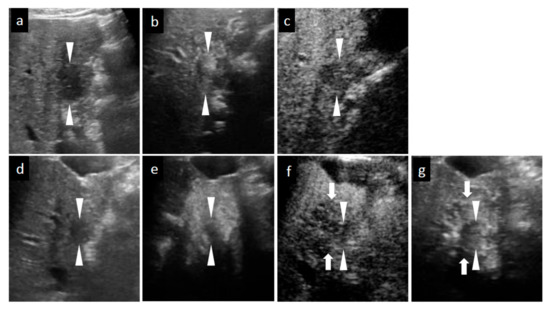

Figure 3.

Grayscale ultrasound (US) and contrast-enhanced US with Sonazoid (SCEUS) images before and after radiotherapy (RT) for an HCC lesion (maximum diameter: 34 mm) in segment III/IV, evaluated as residue after RT. RT was selected as treatment because the lesion was located adjacent to the left portal vein and the tumor size was more than 3 cm (as the maximum diameter). Hypofractionated radiotherapy was performed as the bowel organ was adjacent to the lesion. Before RT (a–c): A hyperechoic lesion was observed using grayscale US (a). This lesion showed hypervascularity during arterial phase (AP) SCEUS (b) and hypoechoic (perfusion defect) during the post-vascular phase (PVP) (c). One month after RT (d–f): The tumor size did not change on grayscale US (d). Using SCEUS, the HCC lesion showed hypervascularity with a partially hypovascular area (curved arrow) during the AP (e) and was hypoechoic during the PVP (f). The surrounding liver parenchyma showed slight hypervascularity during the AP (e) and was hypoechoic during the PVP (f). Four months after RT (g–i): The tumor size did not change on grayscale US (g). Using SCEUS, the HCC lesion showed hypervascularity with a partially hypovascular area (curved arrow) during the AP (h). The surrounding liver parenchyma showed apparent hypervascularity during the AP (h). Both the HCC lesion and the surrounding liver parenchyma appeared as a perfusion defect during the PVP (i). Thirteen months after RT (j–m): The tumor size did not change on grayscale US (j). Using SCEUS, compared with 4 months after RT, the HCC lesion showed hypervascularity during the AP (k). AP SCEUS showed slight hypervascularity of the surrounding liver parenchyma (k). Both the HCC lesion and the surrounding liver parenchyma appeared as a perfusion defect during the PVP (l). The boundary between the HCC and the surrounding liver parenchyma was unclear (l). After re-injection of Sonazoid during the PVP, both the HCC and the surrounding liver parenchyma showed hypervascularity (m). In this case, tumor size reduction and the disappearance of tumor vascularity were not observed during 13 months follow-up. Arrowheads indicate the margins of the HCC lesion. Arrows show the margins of the irradiated surrounding liver parenchyma. Pathological findings obtained from irradiated HCC area (n–p), irradiated surrounding non-tumor area (q,r), and non-irradiated non-tumor area (s,t) at 13 months after RT. For the irradiated HCC area, hematoxylin and eosin (HE) staining showed obvious cell atypia. Specifically, hypercellularity and larger, irregularly shaped nuclei can be seen. The nuclear cytoplasmic ratio is significantly higher. A few multinucleated giant cancer cells can be seen (n). Silver staining showed that reticular fibers have totally disappeared, resulting in poorly differentiated HCC (o). CD34 staining showed strong diffuse expression of CD34, suggesting increased neovascularization resulting from sinusoidal capillarization and the formation of sinusoid vascular endothelium in HCC (p). Irradiated surrounding non-tumor area showing hypervascularity during arterial phase SCEUS (* mark seen in (k)): HE staining showed neither cancer cells nor hepatocytes. Infiltration of inflammation cells (†) and severe fibrosis (‡) are noted (q). CD34 staining showed diffuse expression of CD34 in infiltration of inflammation cells (†) and severe fibrosis regions (‡) (r). Non-irradiated non-tumor area: HE staining showed normal hepatocytes with the normal nucleus shape and the nuclear cytoplasmic ratio. Thin trabeculae are clearly visualized (s). The negative expression of CD34 is seen (t).